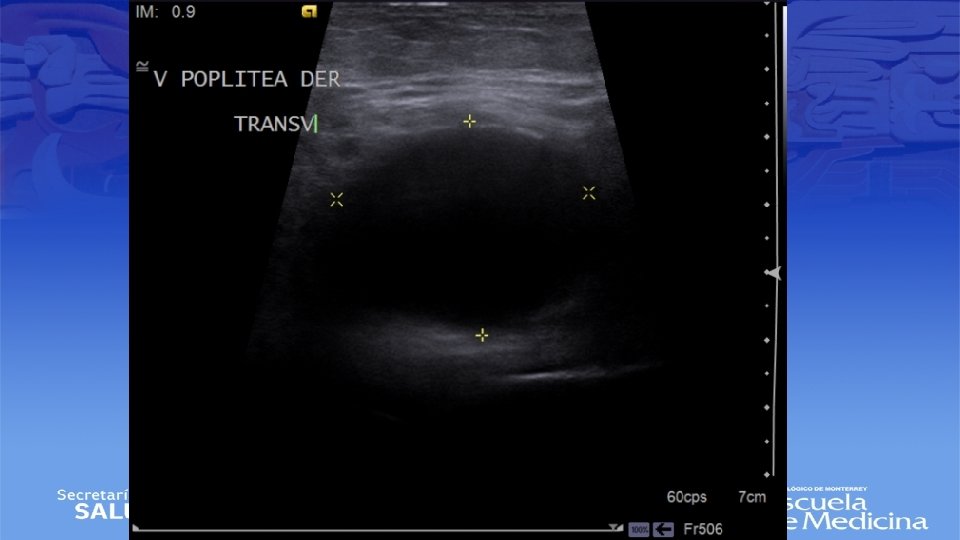

ECO Doppler

Impresión Diagnóstica • IDX: Aneurisma Poplíteo bilateral

Diagnostico • Ultrasonido Doppler, Angiotac, angioresonancia • Arteriografía es mas apropiada para sintomatología aguda